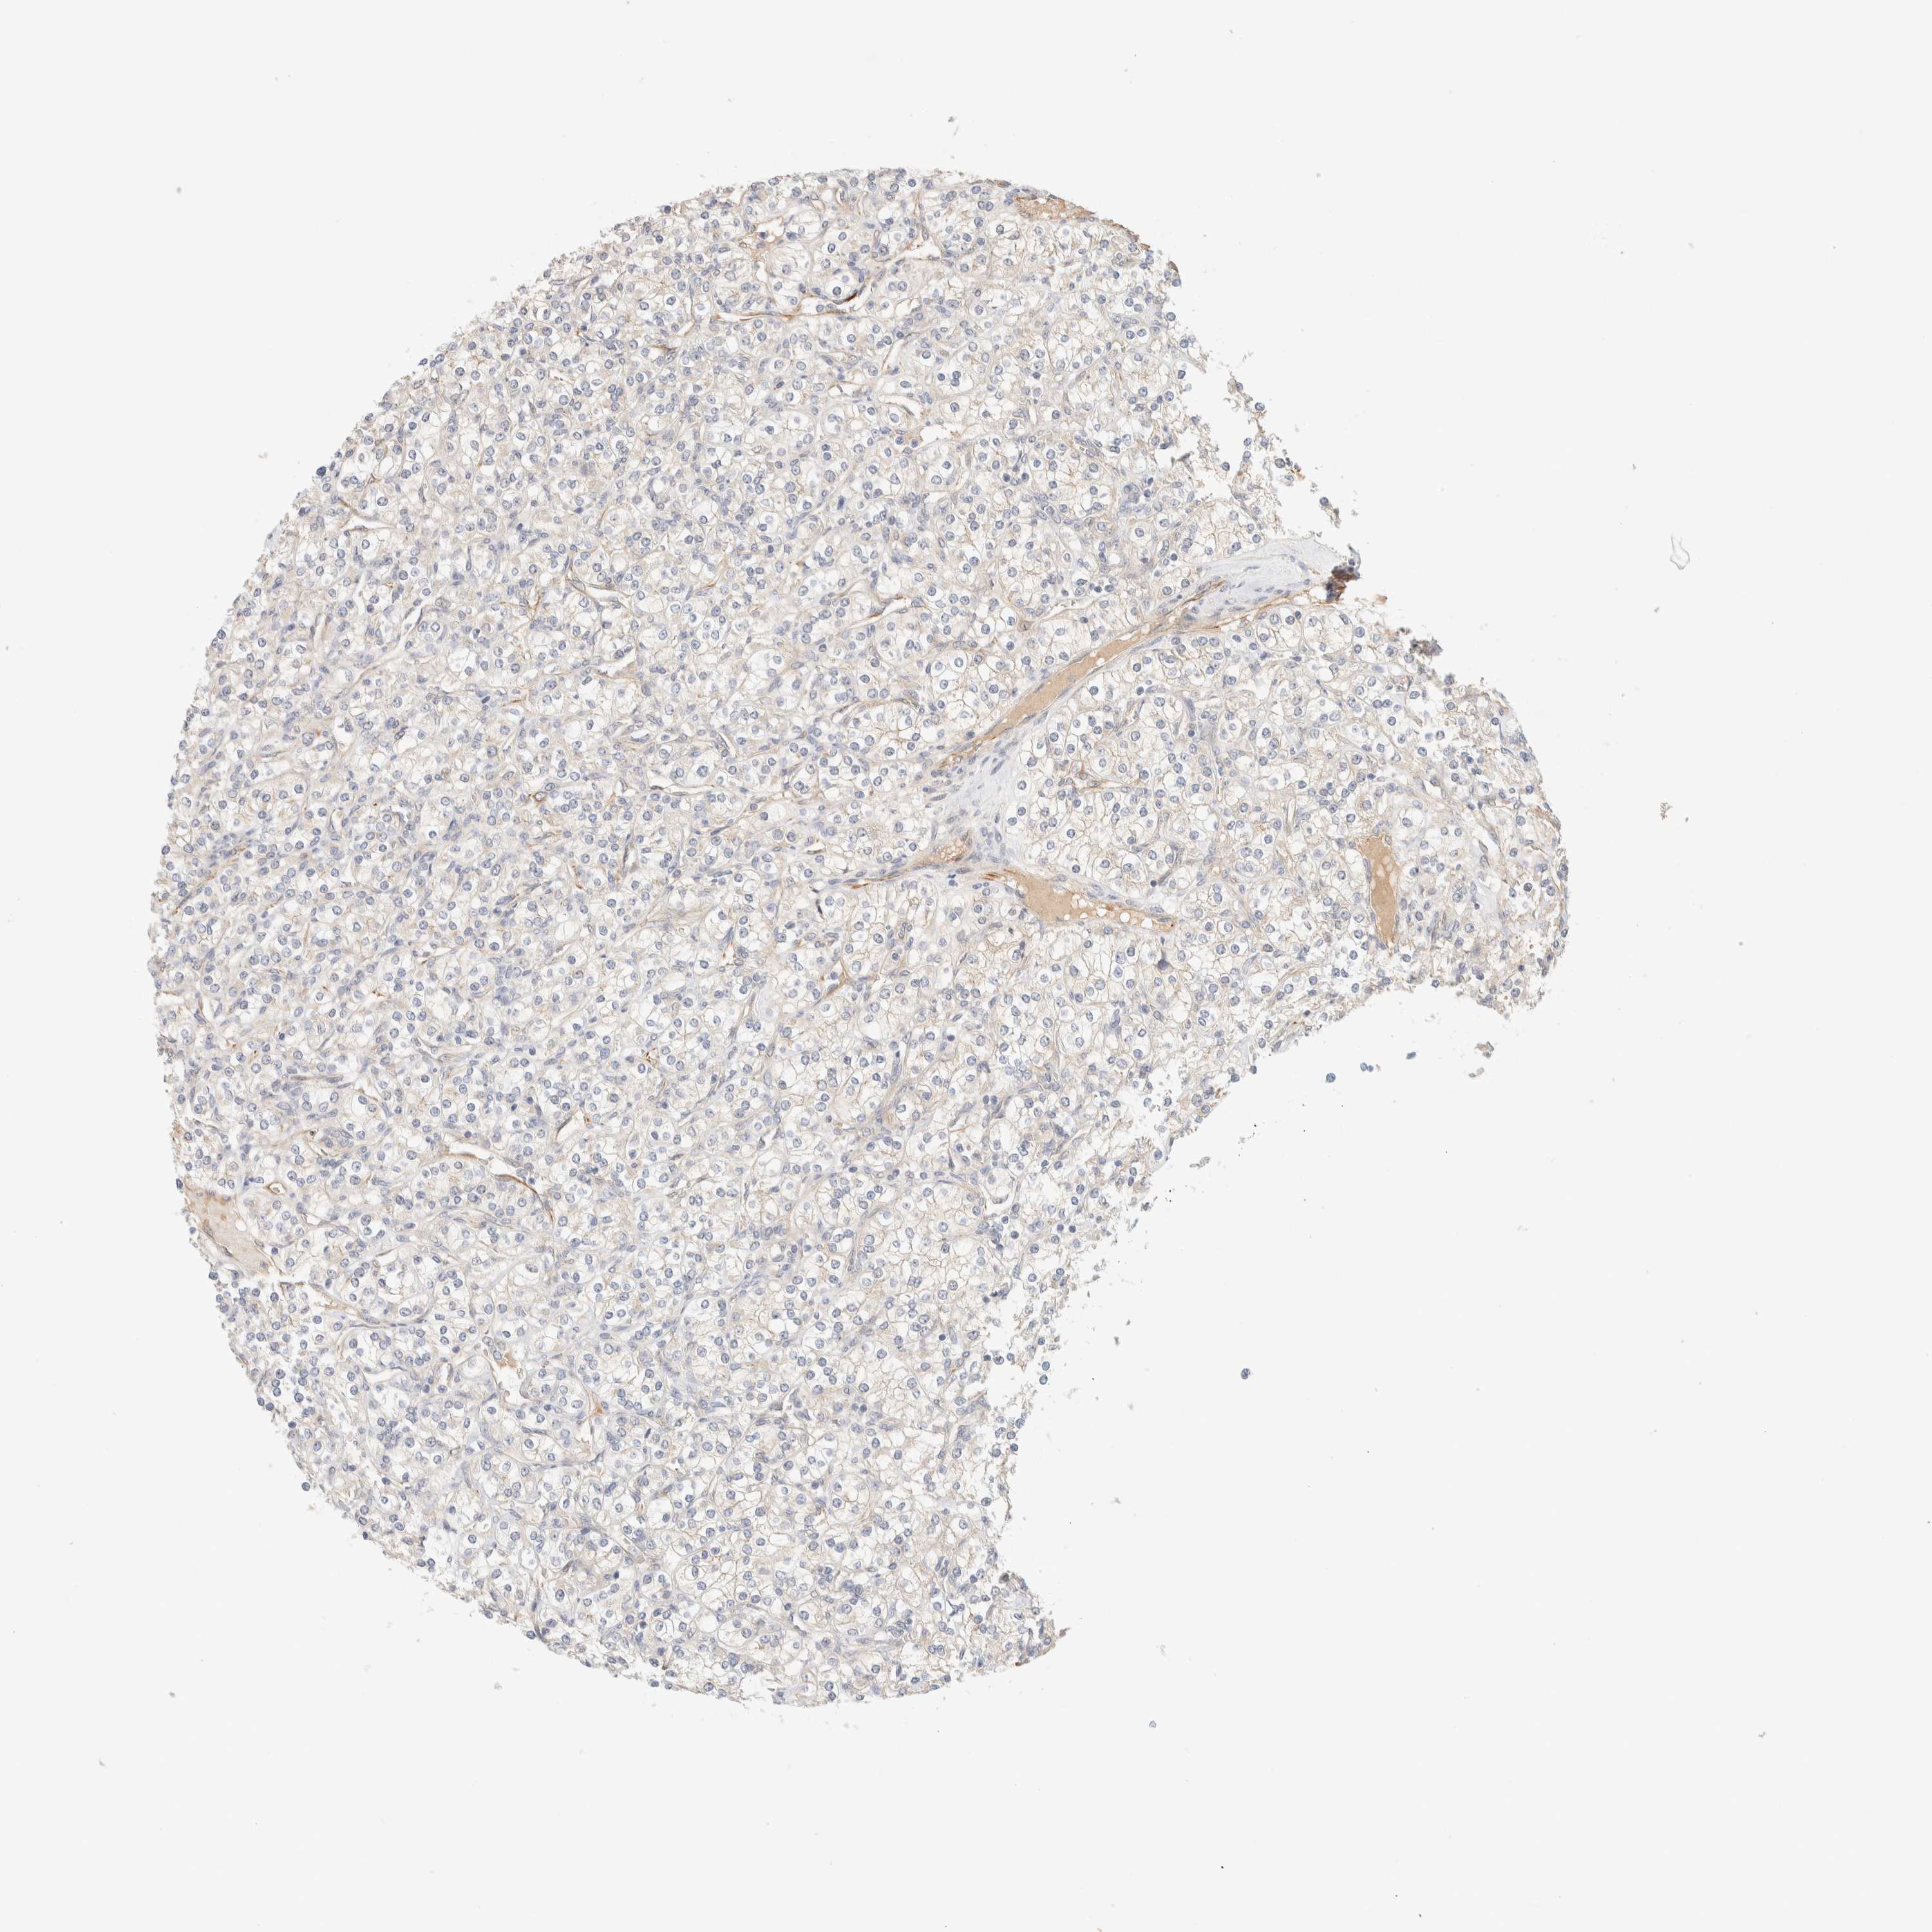

KIDNEY RENAL CLEAR CELL CARCINOMA (TCGA) - Interactive survival scatter ploti

The Survival Scatter plot shows the clinical status (i.e. dead or alive) for all individuals in the patient cohort, based on the same data that underlies the corresponding Kaplan-Meier plots. Patients that are alive at last time for follow-up are shown in blue and patients who have died during the study are shown in red.

The x-axis shows the expression levels (FPKM) of the investigated gene in the tumor tissue at the time of diagnosis. The y-axis shows the follow-up time after diagnosis (years). Both axes are complimented with kernel density curves demonstrating the data density over the axes. The top density plot shows the expression levels (FPKM) distribution among dead (red) and alive patients (blue). The right density plot shows the data density of the survived years of dead patients with high and low expression levels respectively, stratified using the cutoff indicated by the vertical dashed line through the Survival Scatter plot. This cutoff is automatically defined based on the FPKM cutoff that minimizes the p-score. The cutoff can be changed by dragging the vertical line or by entering a cutoff value in the square labeled "Current cut-off".

Under the Survival Scatter plot the p-score landscape (black curve; left axis) is shown together with dead median separation (red curve; right axis). Dead median separation is the difference in median mRNA expression between patients who have died with high and low expression, respectively. It is calculated as follows: median FPKM expression of dead patients with high expression - median FPKM expression of dead patients with low expression. This is intended to aid the user in visually exploring custom cutoffs and the associated p-scores and dead median separation.

Individual patient data is displayed and can be filtered by clicking on one or more of the category buttons on the top of the page. Categories describing expression level and patient information include: high, low, alive, dead, female, male and tumor stages. The scale of the x-axis can be toggled between linear and log-scale by clicking on the "x log" button. Mouse-over function shows TCGA ID, patient information and mRNA expression (FPKM) for each patient.

& Survival analysisi

Kaplan-Meier plots summarize results from analysis of correlation between mRNA expression level and patient survival. Patients were divided based on level of expression into one of the two groups "low" (under cut off) or "high" (over cut off). X-axis shows time for survival (years) and y-axis shows the probability of survival, where 1.0 corresponds to 100 percent.

FAT1 is potential prognostic, high expression is favorable in Kidney Renal Clear Cell Carcinoma (TCGA)

Best expression cut offi

Based on the FPKM value of each gene, patients were classified into two groups and association between prognosis (survival) and gene expression (FPKM) was examined. The best expression cut-off refers the FPKM value that yields maximal difference with regard to survival between the two groups at the lowest log-rank P-value. Best expression cut-off was selected based on survival analysis .

When clicking on this number, the vertical dashed line indicating cut-off, the interactive survival plot, and the Kaplan-Meier curve will be adjusted to show results based on the best expression cut-off.

: 26.8

Average pTPM 54.1

Number of samples 521